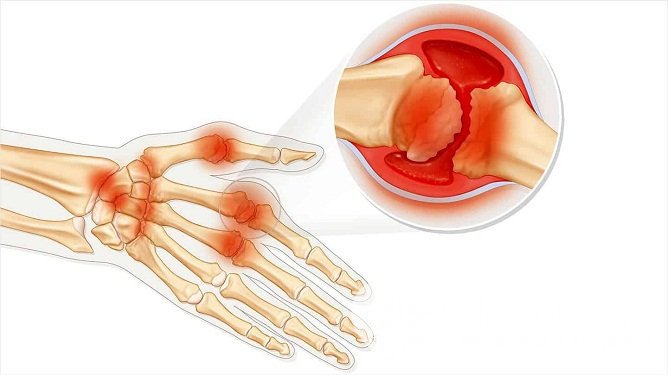

Артрит пальцев рук – одна из самых распространенных форм периферического артрита, при которой воспалительный процесс захватывает пястно-фаланговые и межфаланговые суставы. Первой воспаляется внутренняя синовиальная оболочка сустава, далее патологический процесс распространяется на суставную сумку, хрящи, сухожилия, связки, мышцы и кости.

Артрит пальцев рук – это воспалительный процесс, локализующийся в пястно-фаланговых и межфаланговых суставовПервичный воспалительный процесс обычно развивается на фоне инфекции, ревматической или обменной патологии, реже – на почве перенесенной травмы или хирургического вмешательства. В случае ревматоидного артрита не последнюю роль играет наследственная предрасположенность.

Характерные признаки воспаления суставов пальцев, как правило, наблюдаются на II стадии заболевания, начиная с появления болезненной припухлости, эритемы и крепитации в пораженных суставах, а к рентгенологическим признакам прибавляются множественные сужения межсуставных щелей, кистовидные просветления костной ткани и краевые деформации эпифизов костей. Вывихи, подвывихи и анкилозы суставов выявляют преимущественно на терминальных стадиях заболевания.

Руки, пораженные артритомЛокализация воспалительного процесса и характер деформаций суставов также имеет важное диагностическое значение. При ревматоидном артрите первые признаки воспаления затрагивают второй и третий пястно-фаланговые суставы и третий проксимальный межфаланговый сустав. Позже патологический процесс распространяется на дистальные межфаланговые суставы, а затем на костно-суставные структуры запястья, а также шиловидный отросток локтевой кости. Поражение суставов обычно носит симметричный характер. На поздних стадиях заболевания наблюдаются характерные деформации кисти: искривления пальцев по типу «бутоньерки» или «лебединой шеи», веретеновидная форма кисти и ульнарные деформации, вызванные частичными вывихами пястно-фаланговых суставов.